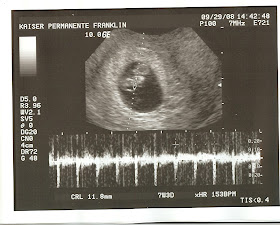

Team Zahrte December 2008

teamzahrte.blogspot.com